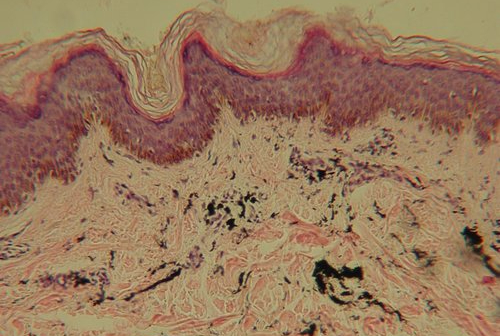

Extensive trauma from the needles reveals that the epidermal-dermal junction is largely destroyed.

Ink particles can be found in the cytoplasm of upper, lower, and basal epidermal cells, as well as dermal macrophages (white blood cells specifically outfitted for healing and immune responses within the dermis).

Extracellular particles drain through the weakened collagen netting of the dermis into the lymphatic system, leaving the skin.

The basement membrane of the dermal-epidermal junction is slowly rebuilding. In the dermis, ink containing cells are concentrated along the epidermal border and are closely surrounded by collagen.

No pigments are found in the surrounding lymphatic vessels, nor extracellularly.

Dermal macrophages containing ink particles are spread throughout the upper portion of the dermis, and each cell is tightly surrounded by the rebuilt collagen network.